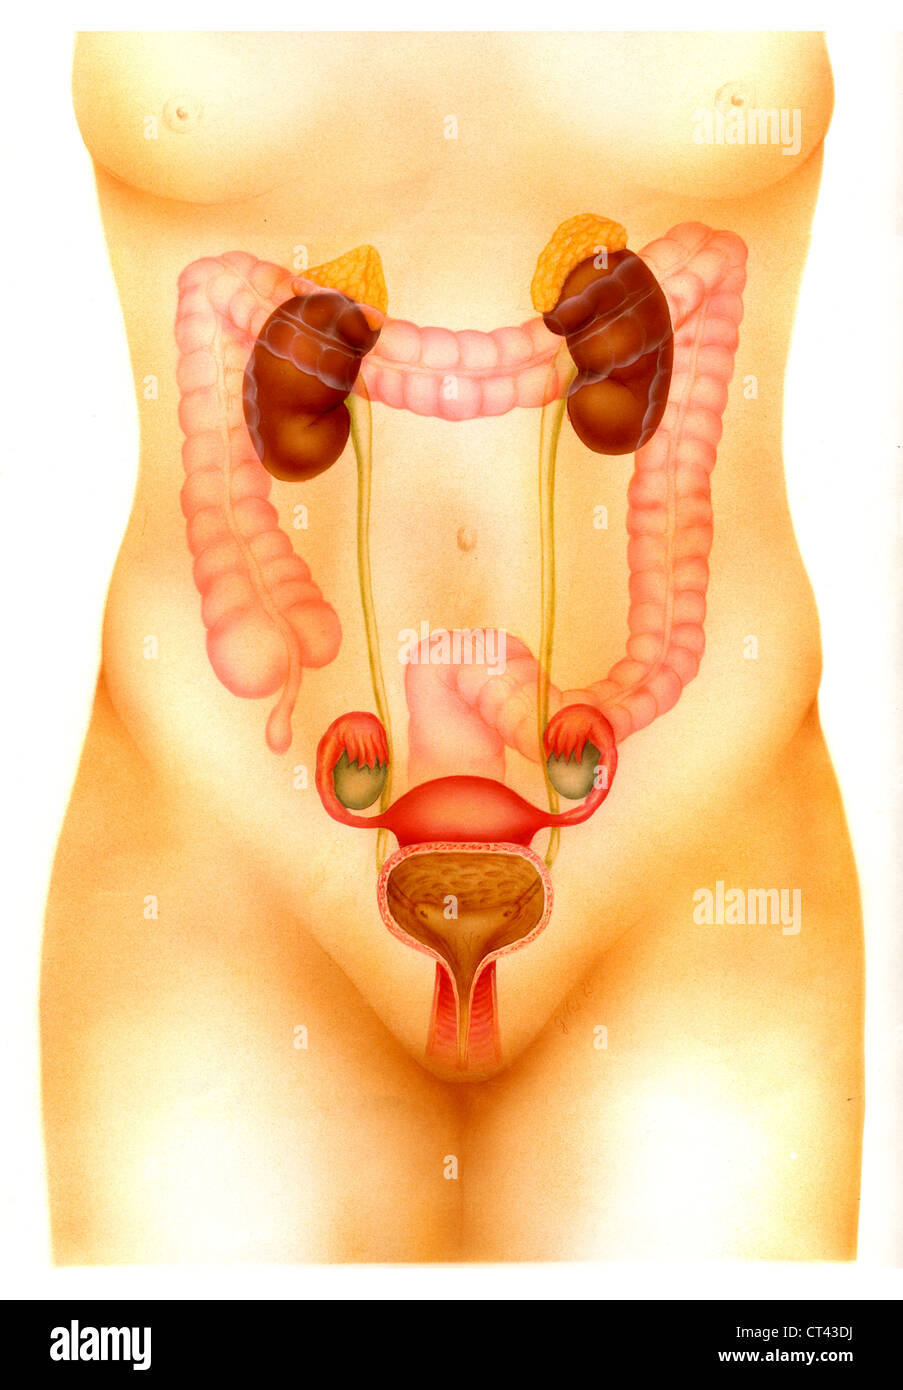

Tractus génito-urinaire féminin Banque D'Imageshttps://www.alamyimages.fr/image-license-details/?v=1https://www.alamyimages.fr/photo-image-tractus-genito-urinaire-feminin-49263022.html

Tractus génito-urinaire féminin Banque D'Imageshttps://www.alamyimages.fr/image-license-details/?v=1https://www.alamyimages.fr/photo-image-tractus-genito-urinaire-feminin-49263022.htmlRMCT43DJ–Tractus génito-urinaire féminin